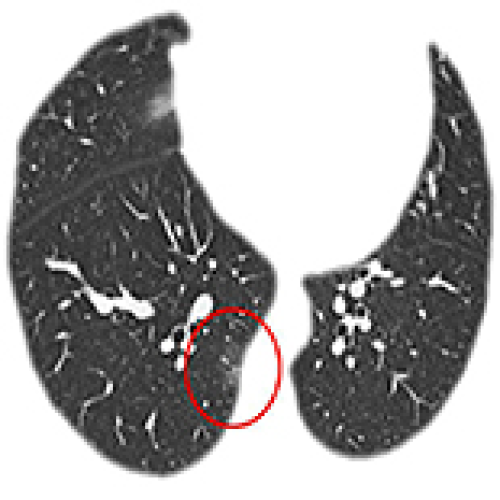

06 Oct 2021 : Database Analysis

A Simple Clinical Prediction Tool for COVID-19 in Primary Care with Epidemiology: Temperature-Leukocytes-CT Results

Wanming Hao, Long Zhao, Xinjuan Yu, Song Wu, Weifeng Xie, Ning Wang, Weihong Lv, Akshay Sood, Shuguang Leng, Yongchun Li, Qing Sun, Jun Guan, Wei Han

DOI: 10.12659/MSM.931467

Med Sci Monit 2021; 27:e931467

3,023 988 0

3023 988 0